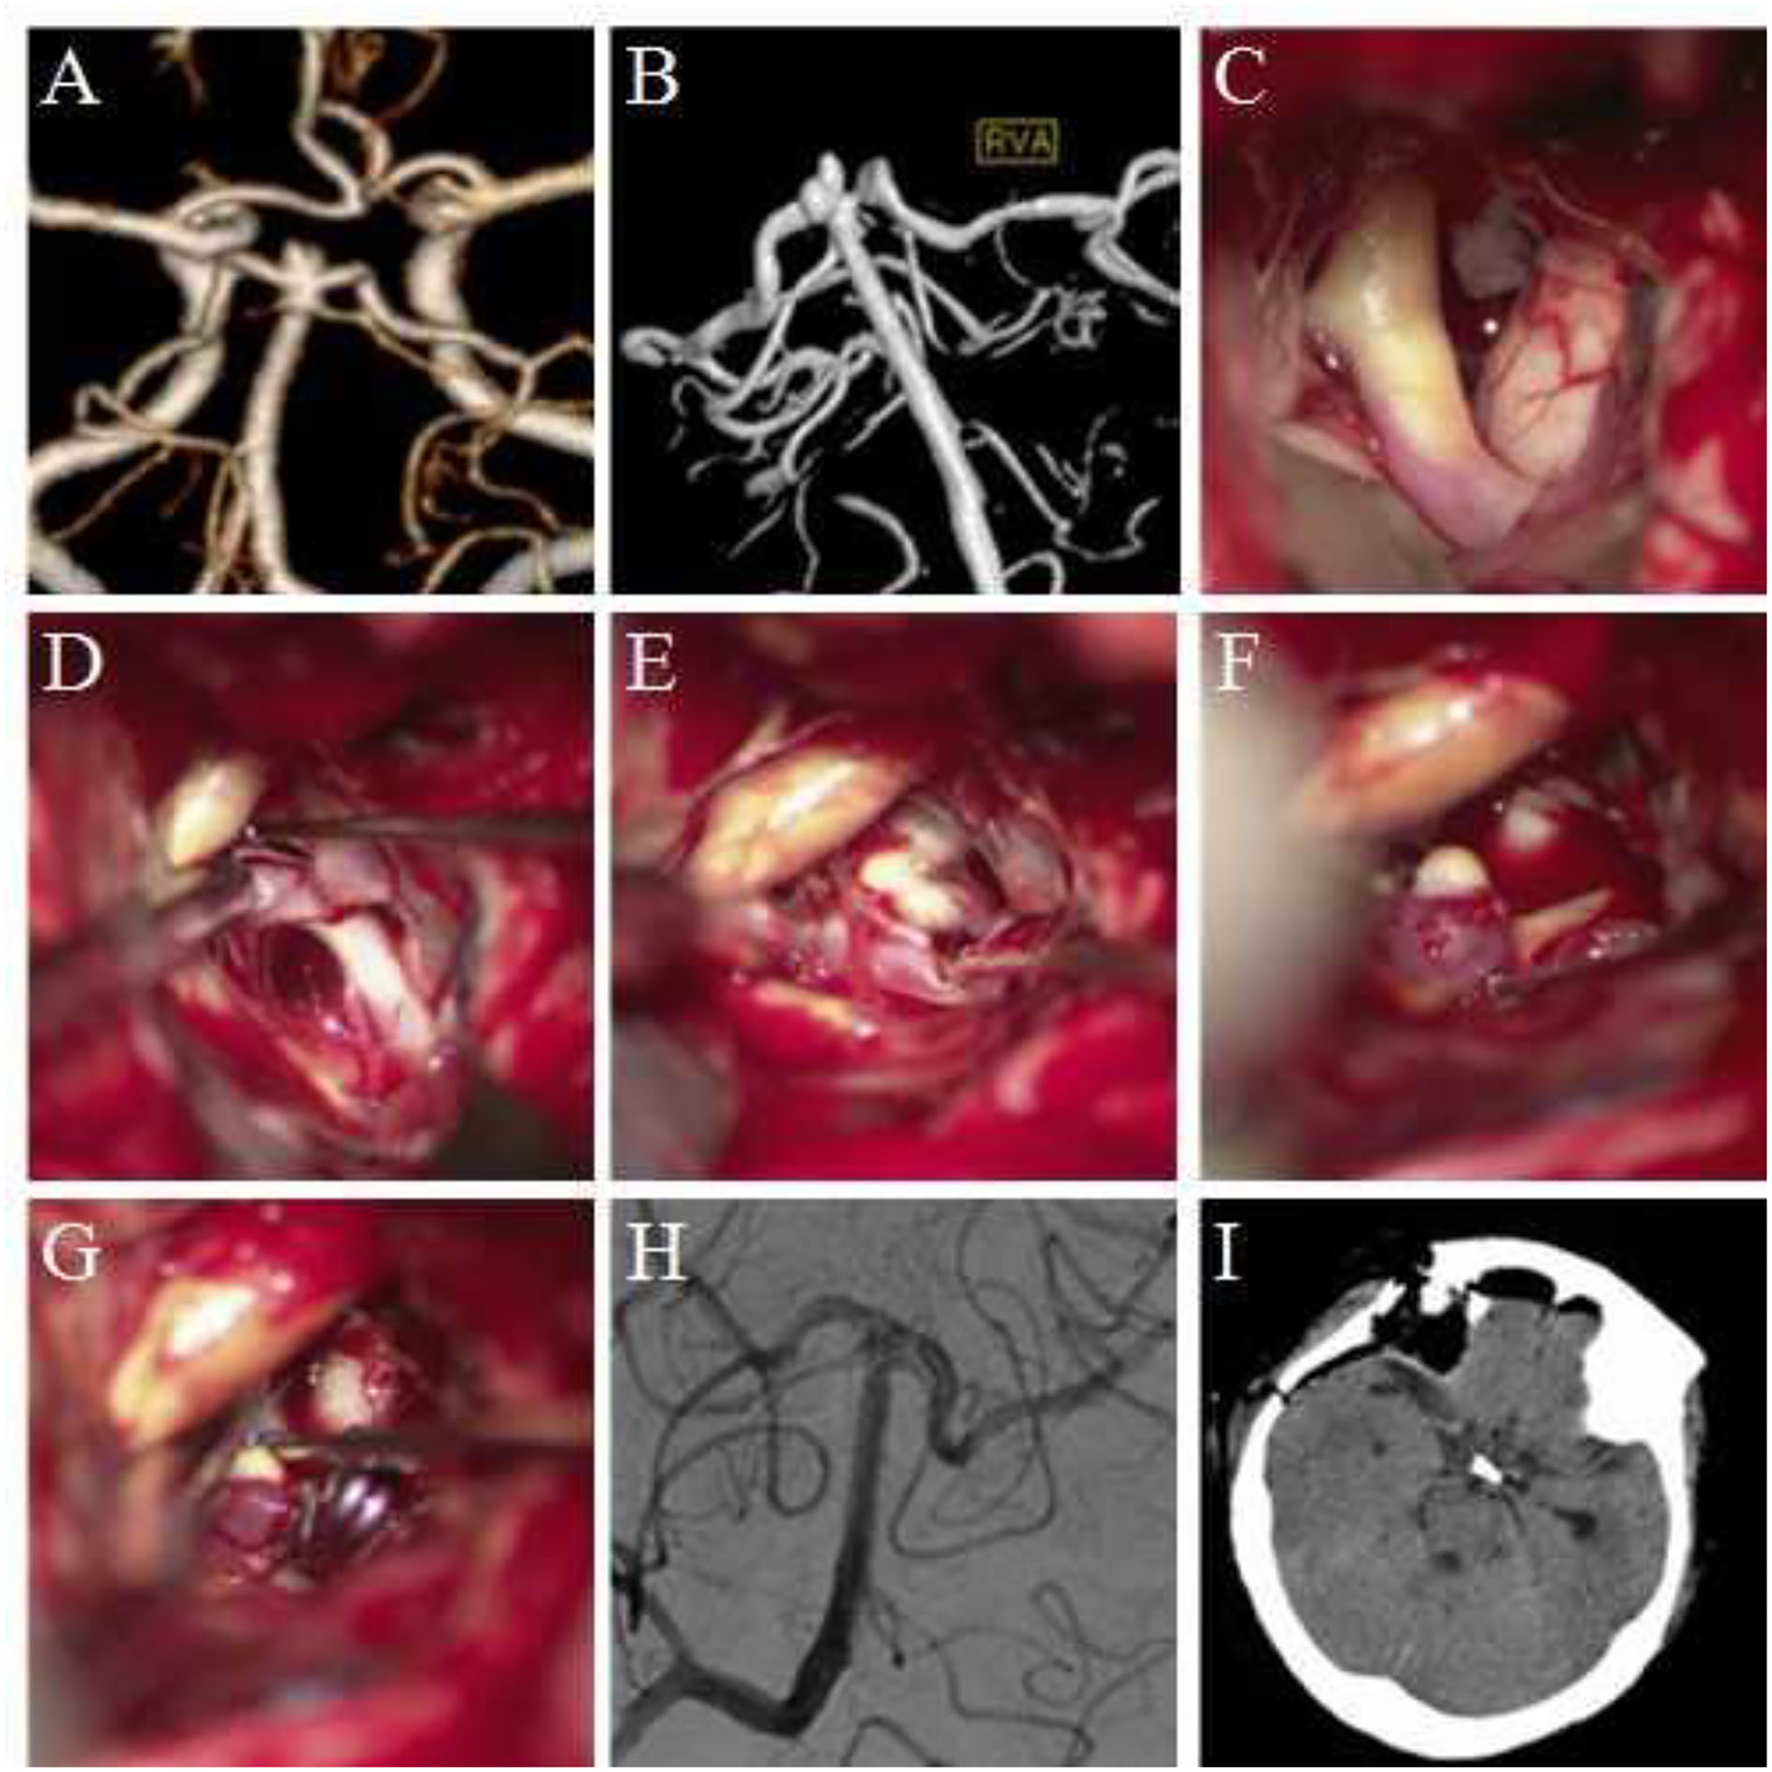

FIGURE 1

Figure 1. Clipping of basilar artery apical aneurysm via the Dolenc approach. (A,B) Preoperative computed tomography angiography (CTA) and digital subtraction angiography (DSA) revealed a basilar artery apical aneurysm; the aneurysm was lobulated. (C) During surgery, the internal carotid artery and the posterior clinoid process of the surgery side were exposed. (D) The internal carotid artery was pulled medially, and the exposure range was increased. The P1 segment of the posterior cerebral artery and its perforating arteries were visible. (E) The basilar artery was exposed along the posterior cerebral artery to the top of the basilar artery. The aneurysm was exposed, and the sub-aneurysm was visible. (F) The aneurysm was completely exposed, and sub-aneurysms were visible. (G) The neck of the aneurysm was clipped. The basilar arteries, bilateral posterior cerebral arteries, and superior cerebellar arteries were explored, and no vascular damage was observed. (H) Intraoperative DSA revealed no development of aneurysm and no vascular damage. (I) Re-examination was performed using the head CT within 12 h after surgery.